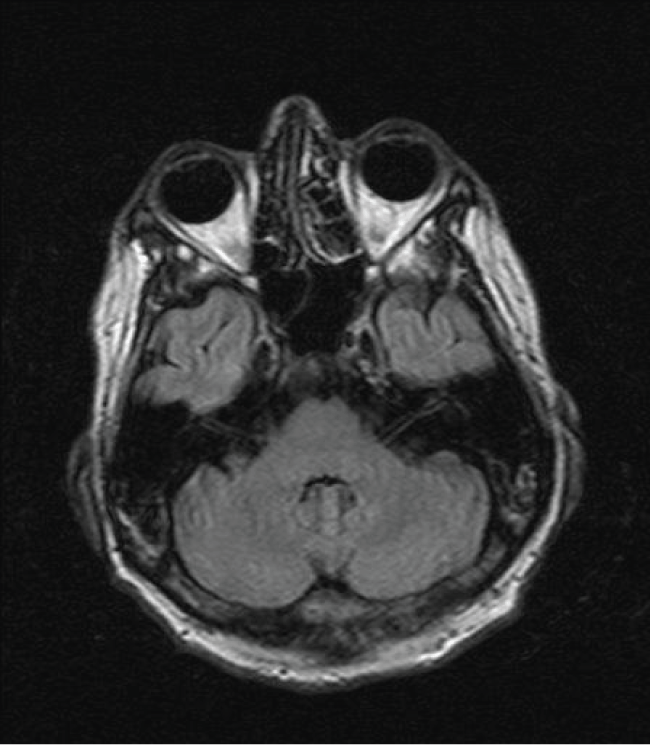

On hospital day 21, an MR brain demonstrated hyperintense signal on FLAIR (Figure 1) and T2 sequences in both cerebellar dentate nuclei, dorsal pons and central tegmental tract. Diffusion weighted images (DWIs) showed bright signal in both cerebellar dentate nuclei (Figure 2) with corresponding high apparent diffusion coefficient (ADC) consistent with vasogenic edema. The lesions did not demonstrate contrast enhancement.

Figure 1: Axial FLAIR image demonstrates bilateral symmetric hyperintense signal in the dentate nuclei (large arrow) of the cerebellum and both central tegmental tracts (small arrow).

Neurology consultation found the patient to be alert, oriented with intact cognition but very dysarthric speech. Cranial nerve exam was significant for coarse horizontal nystagmus to both left and right lateral gaze. He was confined to bed and unable to feed himself because of incapacitating truncal and appendicular ataxia. Based on the characteristic MR findings of hyperintense signal most notable in both cerebellar dentate nuclei, a diagnosis of metronidazole-induced cerebellar toxicity was made. Metronidazole was promptly discontinued. Lumbar puncture was not performed due to an elevated INR secondary to his hepatic dysfunction.

Patients with metronidazole central nervous system (CNS) toxicity most commonly present with dysarthria and ataxia. However, symptoms may also include altered mental status, seizures, and visual disturbances [1]. MR is the modality of choice in identifying CNS toxicity. Structures most vulnerable to metronidazole toxicity include both cerebellar dentate nuclei but also the midbrain (tectum, red nucleus, tegmentum around the periaqueductal gray matter), dorsal pons, superior olivary nucleus and the splenium of the corpus callosum [4].

On FLAIR and T2 weighted images, common findings include hyperintense lesions of the cerebellar dentate nuclei, midbrain, dorsal pons, corpus callosum, and cerebral white matter. A pattern consistent with vasogenic edema is usually identified with bright signal on diffusion-weighted images (DWI) and high apparent diffusion coefficient (ADC). These MR findings are most conspicuous in bilateral cerebellar dentate nuclei and resolve in conjunction with clinical improvement upon drug discontinuation. Permanent residual neurologic deficits have been reported highlighting the need for prompt recognition.